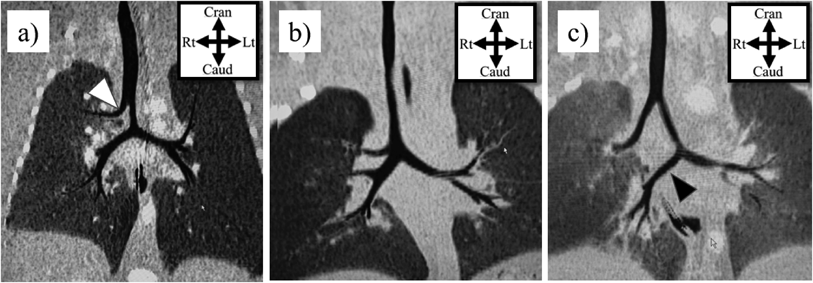

気管や気管支の先天異常を知るうえで,気管分岐異常の理解は欠かせない.気管分岐異常には,気管気管支(tracheal bronchus),気管三分岐(bronchial trifurcation),bridging bronchusなどがある(Fig. 2).

Pediatric Cardiology and Cardiac Surgery 37(4): 283-294 (2021)

Fig. 2 Tracheobronchial anomaly on coronal reformatted computed tomography (frontal aspect)

a) Tracheal bronchus (white arrowhead), b) Trifurcation, c) Bridging bronchus (black arrowhead)

気管気管支とは,気管分岐部よりも上部の気管から上葉領域へ分枝する異常な気管支を指し,上葉の区域枝をすべて出すパターン(ブタではこの分岐パターンのため‘pig bronchus’と呼称される)から,上葉の一部区域のみに分枝するパターン(displaced),通常の上葉枝が右主気管支から分枝しているにもかかわらず余剰な分枝があるパターン(supernumerary),気管気管支の先が盲端となるパターン(rudimentary)など様々なタイプがある3, 8).これらは気管の右側で発生しやすいことが特徴的である9, 10).また,気管三分岐は気管分岐部から右の上葉枝が分岐するもので,気管気管支の亜型と考えられる.そして,bridging bronchusとは気管気管支に加えて,気管分岐部が通常よりも尾側・左方に偏位し,右中葉・下葉に向かう気管支が椎体をまたいで左から右に横走する気管支を指す11).これらの気管分岐異常は,胎生4~5週の間の肺芽・気管支芽の発生異常に起因すると考えられている.先天性気管狭窄も同時期の発生異常に起因することから,気管狭窄に気管気管支などが合併することは容易に理解できる.実際,気管気管支は先天性気管狭窄の11.9~24.7%の症例で認められる12).一方,気管気管支は症状のない一般人1%程度にも認められ,先天性気管狭窄に比して発生頻度が非常に高い9, 10).したがって,先天性気管狭窄の発症には,気管気管支の発生異常に,さらになんらかの因子が加わっていると推定される.